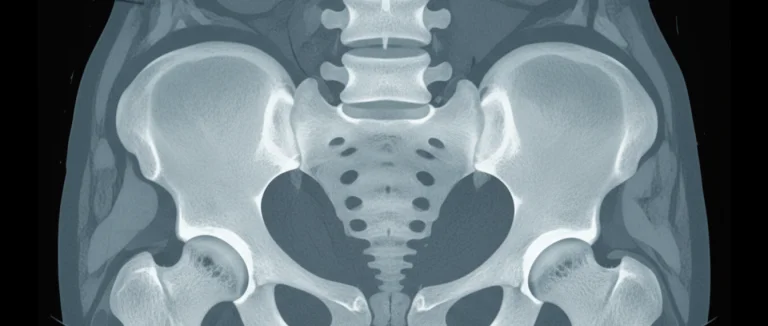

Процедура начинается с тщательной подготовки пациента, включающей сбор аутологичных стволовых клеток из костного мозга или жировой ткани. Затем клетки обрабатываются в стерильных условиях и вводятся под контролем визуализации.

- Инъекция под КТ или УЗИ‑контролем в целевой сегмент поясничного отдела.